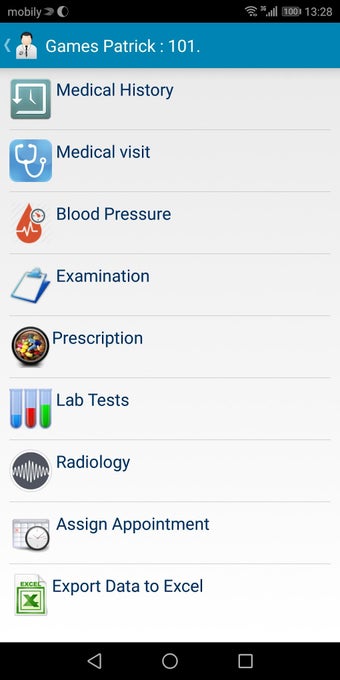

The Android Medical Records App by MedClin is a free medical records tracker app that allows users to store anamnesis, patient records, patient history, and health information. It is easy to use and provides numerous features such as username and password authentication, exporting medical data to Excel Sheet, and the ability to attach medical documents of any type. The app also has a smart search feature that allows users to search for patient information by name or ID, and even capture a photo for their profile.

In addition, the app has a blood pressure module that measures systolic, diastolic, and pulse, and allows users to export blood pressure reports to either PDF or graphs. The app also has a blood glucose (sugar) module that records blood sugar values and allows users to export blood glucose reports to either PDF or graphs. Users can also send blood pressure and blood sugar reports to their doctor. The app is compatible with multiple screens, including phones and tablets, and works on Chromebook systems. Overall, the Android Medical Records App is a great tool for patients and physicians alike for managing patient information and medical records.